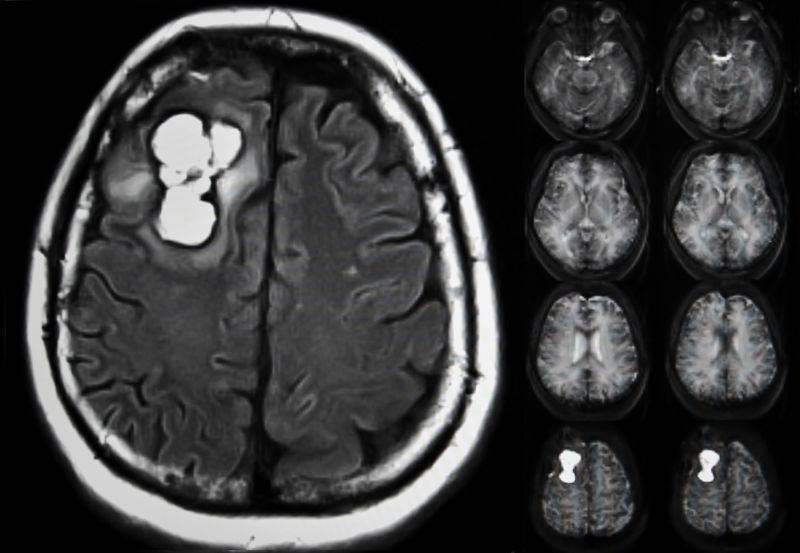

1- MRI یا سی تی اسکن مغز

MRI بهترین روش تصویربرداری برای تشخیص تومورهای مغزی است. اگر امکان MRI نباشد، سی تی اسکن (توموگرافی کامپیوتری) میتواند جایگزین مناسبی باشد. قبل از انجام این آزمایشها، ماده حاجب برای نمایش واضحتر تومور به یکی از سیاهرگهای شما تزریق میشود.

این تصویربرداریها میتوانند اندازه و محل دقیق تومور را با جزئیات مشخص کنند. پزشک ممکن است برای بررسی انتشار احتمالی تومور، بخشهای دیگر بدن مانند ریهها، روده بزرگ یا سینه را نیز بررسی کند.